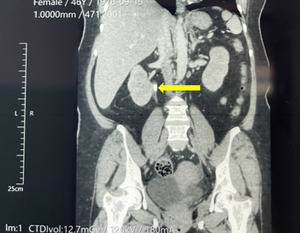

A 46-year-old woman with a past medical history of type 2 Diabetes Mellitus treated with metformin presented with three days of abdominal pain radiating towards the back. The pain was partially relieved by bending forward and aggravated with food. Several episodes of nausea and vomiting accompanied the pain. On physical examination, there was tenderness to palpation in the epigastric area. Her laboratory values at the time of presentation are described in Table 1. Her amylase (245 u/L) and lipase (236.6 u/L) were elevated among those. Her arterial blood gases with pH 7.42, Pc02 34.6 mmHg, p02 77.6 mmHg, bicarbonate 22.1 mmol/L. BISAP score was 1. She was treated with intravenous fluids and analgesics. A computerized tomography (CT) scan of the abdomen and pelvis with contrast revealed bilateral renal microlithiasis, right hydroureteronephrosis secondary to calculus in the renal pelvis (Figure 1), Balthazar C pancreatitis (inflammatory changes in pancreas and peripancreatic fat) and left adnexal cyst.